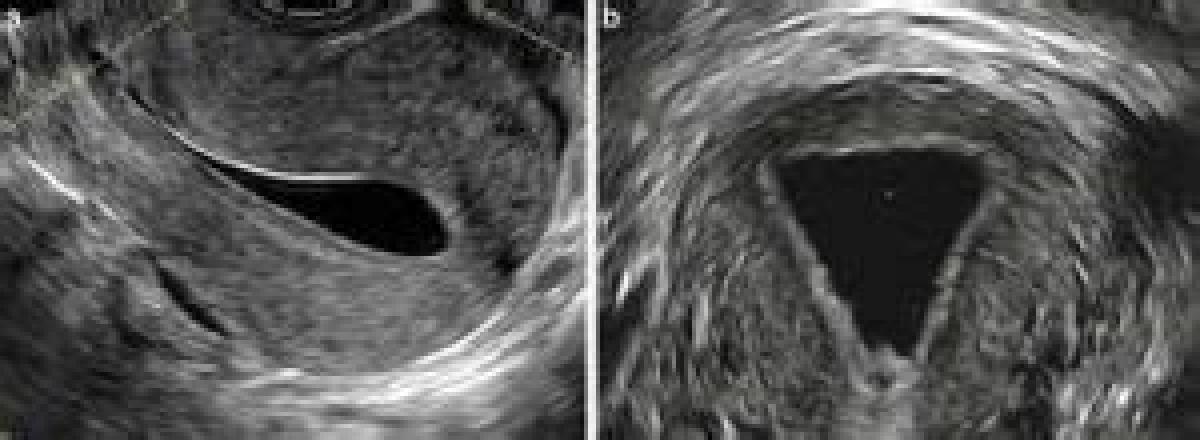

اولتراسونوگرافی میتواند تصویری را از رحم و فیبروئیدها یا پولیپهای احتمالی ارائه دهد. سالین یا ژل در داخل حفره رحم تصویر اولتراسوند را واضحتر میکند. این روش سونوگرافی اینفیوژن سالین (saline infusion sonography; SIS) نامیده میشود. معمولا، این تصویر فقط دوبعدی است. امروزه، ایجاد کردن یک تصویر سهبعدی امکانپذیر شده تا نوع ناهنجاری بهتر بتواند دیده شود.